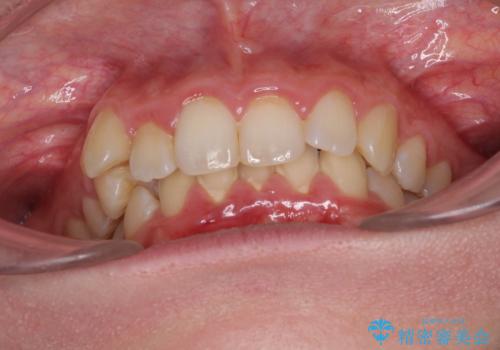

- 八重歯を気にして来院された患者様です。

八重歯の後ろの歯を1歯抜歯し、補助装置(リンガルアーチ)を用いて八重歯の位置を改善し、その後インビザラインにより矯正治療を行うこととしました。

下顎前歯が1本欠損したスリーインサイザーという状態であるため、上下の前歯の咬み込みが深くなったり、奥歯の咬み合わせが理想的なものとならなかったりという仕上がりになってしまいます。

前歯の見た目や奥歯の咬み合わせに、患者様が違和感を感じない状態として治療を終えました。